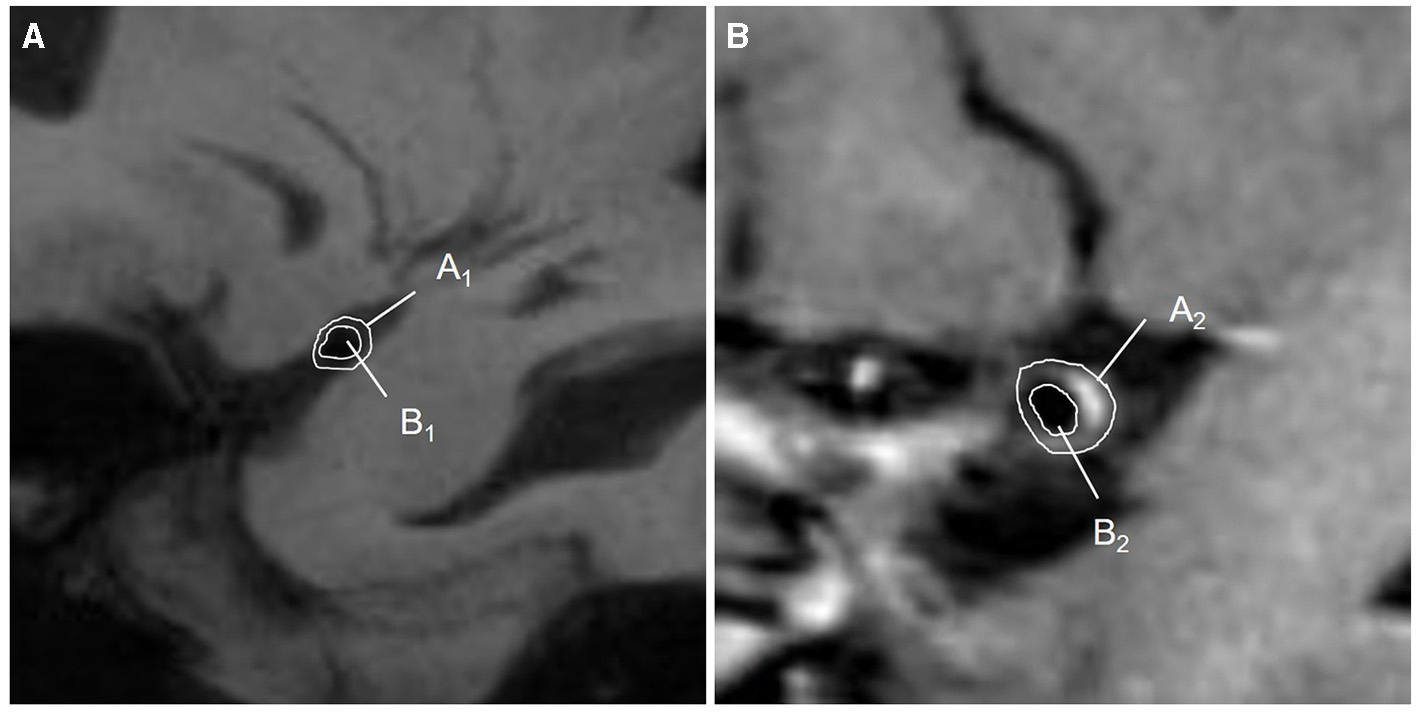

Traditional parameters of the MCA-M1 plaque

A plaque was defined as eccentric or focal vessel wall thickening compared with its distal, proximal, or contralateral vessel segments (24). A culprit plaque was defined as the only plaque in the M1 segment of the affected side or the most stenotic one when there were multiple plaques in the vascular territory of the stroke (12, 25). If there were discrepancies in plaque recognition between two observers, they should invite a senior physician (who has worked in neuroradiology for 20 years) and work together to determine the final measurement. The plaque distribution on the short-axis view was segmented as the vessel wall's superior, dorsal, inferior, and ventral sides. Plaque enhancement was defined as a signal on enhanced plaque imaging higher than on an HR-VWI T1WI sequence and the contralateral vessel (5, 26). The thickest plaque was selected to measure the lumen diameter, and the lumen diameter at the reference sites was measured, too. Both the vessel area (VA) and lumen area (LA) at the lesion and reference sites were traced manually, as shown in Figure 4. Each indicator could be calculated as follows: (1) Wall area (WA) = VA-LA; (2) plaque area = WA lesionsite – WA referencesite; (3) wall area index = WA lesionsite/WA referencesite; (4) plaque burden = (VA lesionsite – LA lesionsite)/VA lesionsite × 100% (27, 28); (5) stenosis rate = (1 – lumen diameter at the lesion site/lumen diameter at the reference site) × 100% (29). (6) The remodeling index (RI) was defined as the ratio between the LA at the lesion site and the reference site. If RI ≥1.05, it was defined as positive remodeling (PR); if RI ≤0.95, it was defined as negative remodeling (NR); if 0.95 < RI < 1.05, it was defined as intermediate remodeling. NR and intermediate remodeling were collectively called non-positive remodeling (non-PR) (30).

Figure 4

Diagram of quantitative measurements on HR-VWI. (A) The lumen at the reference sites was shown on HR-VWI. Area A1 = VA1; area B1 = LA1; WA1 = A1-B1; (B) The lumen at the lesion sites was shown on HR-VWI. Area A2 = VA2; area B2 = LA2; WA2 = A2-B2; plaque area = WA2 – WA1.VA, vessel area; LA, lumen area; WA, wall area.